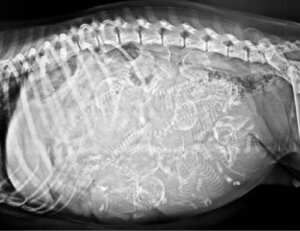

Wygląd szczeniaka nie mógłby być bardziej nietypowy. Był malutki, miał białą sierść, na jego czole znajdowało się jedno ogromne oko, a z każdej strony jego pyszczka wystawał jeden język. Ponieważ oko zajmowało tak dużo miejsca, nie dało szans na to, aby w czaszce psa wykształcił się nos ani pyszczek.

Charakteryzuje je obecność jednego oka umieszczonego na środku czoła, które pojawia się w wyniku połączenia obu oczu oraz postać alobarna jednokomorowego przodomózgowia, czyli braku podziału mózgowia na dwie półkule.